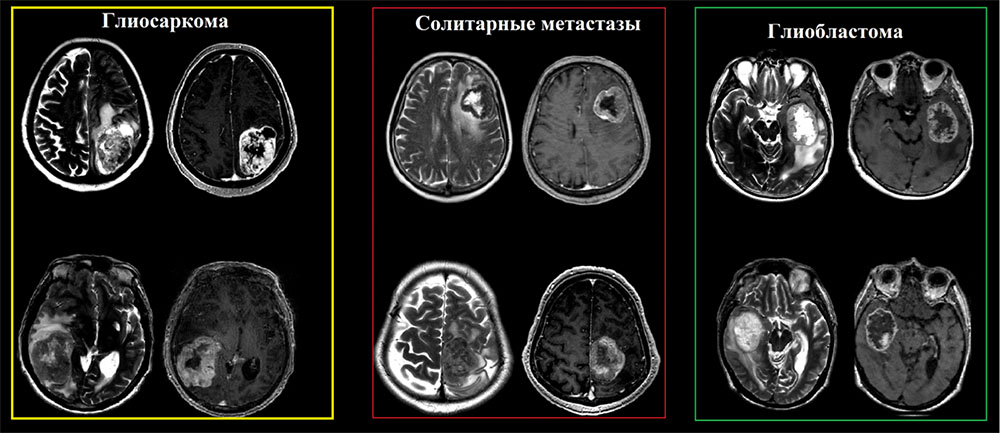

Частота встречаемости глиосарком составляет от 1% до 8% от всех злокачественных глиом, пик встречаемости 4-6 декады жизни с преобладанием мужской популяции, с медианой выживаемости около 9 месяцев. Глиосаркомы имеют общие и практически не отличимые визуализационные характеристики в сравнении с классическими глиобластомами и в большинстве случаев диагноз устанавливается после иммуногистохимического исследования. Стоит отметить, что глиосаркома обладает более высокой тенденцией к экстракраниальному метастазированию (наблюдаются в 30% случаев), последние включают висцеральные органы и спинной мозг.

N.В.! В зависимости от количества саркоматозной и глиальной ткани отмечаются вариации, при этом если саркоматозная ткань преобладает, то опухоль подобна метастазу (хорошо отграниченная и плотная), в случае превалирования астроцитарного(нейроглиального) компонента опухоль идентична классической глиоблатоме (Louis DN, Ohgaki H).

Глиосаркома должна быть включена в дифференциальный ряд любой опухоли, которая, по-видимому, является интрааксиальной, но при этом «интимно» прилежит к твердой мозговой оболочки  и демонстрирует гетерогенные визуализационные характеристики на T2-взвешенных изображениях.